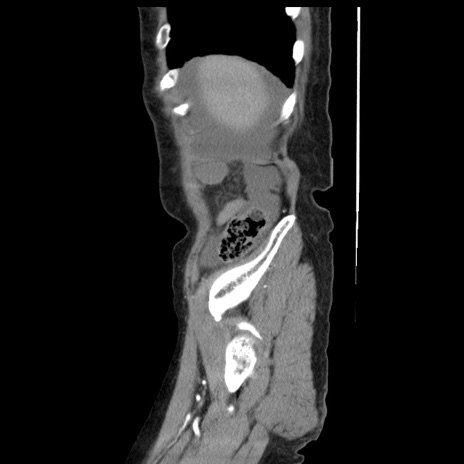

症例1(矢状断像)

【症例】80歳代女性

【主訴】腹痛

【現病歴】8時間前から腹痛あり来院。

【既往歴】糖尿病、脂質異常症、子宮体癌にて子宮全摘術

【身体所見】意識清明・会話良好だが腹痛で苦悶様、全腹部にわたって反跳痛と圧痛あり

【データ】WBC 13600、CRP 0.14、LDH 224、CK 90